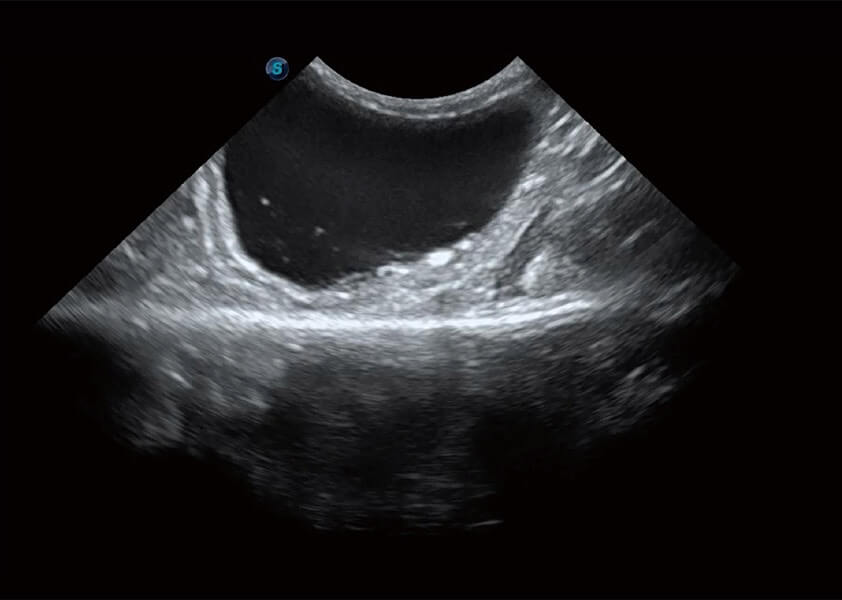

ProPet 60 作为一款高端台式动物超声设备,为动物医生的日常诊断提供了一系列贴合动物临床需求、解决临床实际问题的高级成像功能。凭借全系列高清探头,满足医生对腹部、心脏、生殖、浅表、肌骨等成像的所有需求,切实帮助您提升检查效率,提高诊断信心。

动物是人类最亲密的朋友和最值得信赖的伙伴。DB中国旗舰官方网站也一直致力于探索动物专用的超声影像解决方案。 全新推出的ProPet系列,是DB中国旗舰官方网站在动物超声影像智能化、专业化、精准化的一次跨越式革新。动物不能用言语来表述自己的不适,通过超声影像,ProPet系列搭建了动物医生与不同物种沟通的“桥梁”,为动物医生注入了“治愈之力”。